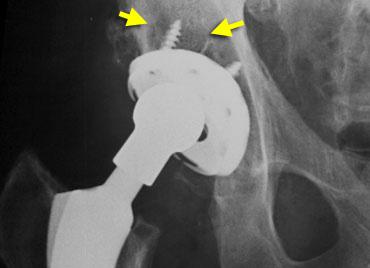

The case on the left is for several reasons not ideal :

– Vị trí cup quá cao và quá nghiêng về phía ngoài.

– Độ nghiêng sang bên quá nhiều.

– Lượng xi măng chèn lấp quá nhiều.

– Các vít được đặt quá nằm ngang (ứng suất quá lớn).

– Vùng thấu quang ở vùng II và III > 2 mm.

Đặc biệt, vùng thấu quang ở các khu vực này rất gợi ý đến tình trạng lỏng khớp.

Trong quá trình theo dõi, sự di chuyển lên trên kèm theo độ nghiêng tăng dần được ghi nhận, gây ra gãy vít cố định.